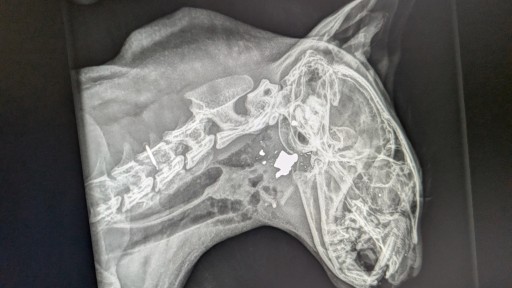

Es klingt wie ein schlechter Film - für ein Ehepaar aus dem Saarland, das im französischen Alsting lebt, ist es bittere Realität: Ihr geliebter Kater wurde erschossen - mutmaßlich von einem Nachbarn. Nun ermittelt die Staatsanwaltschaft.